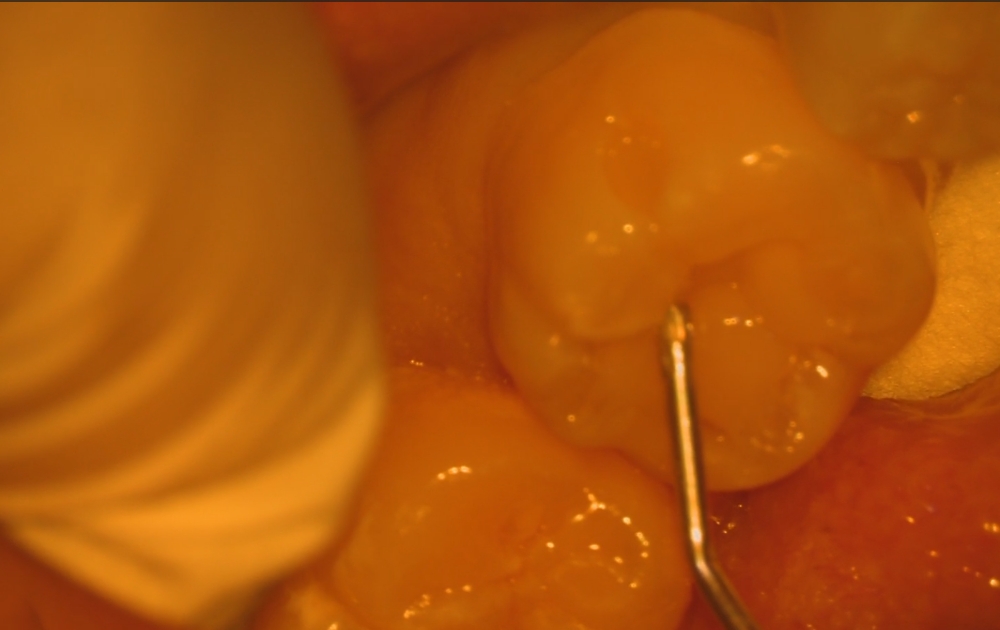

• 2.外側を少しずつ削ることで、内側に広く虫歯が進行していることが分かります。見た目以上に深いケースも多く、慎重な確認が必要です。

2.外側を少しずつ削ることで、内側に広く虫歯が進行していることが分かります。

見た目以上に深いケースも多く、慎重な確認が必要です。